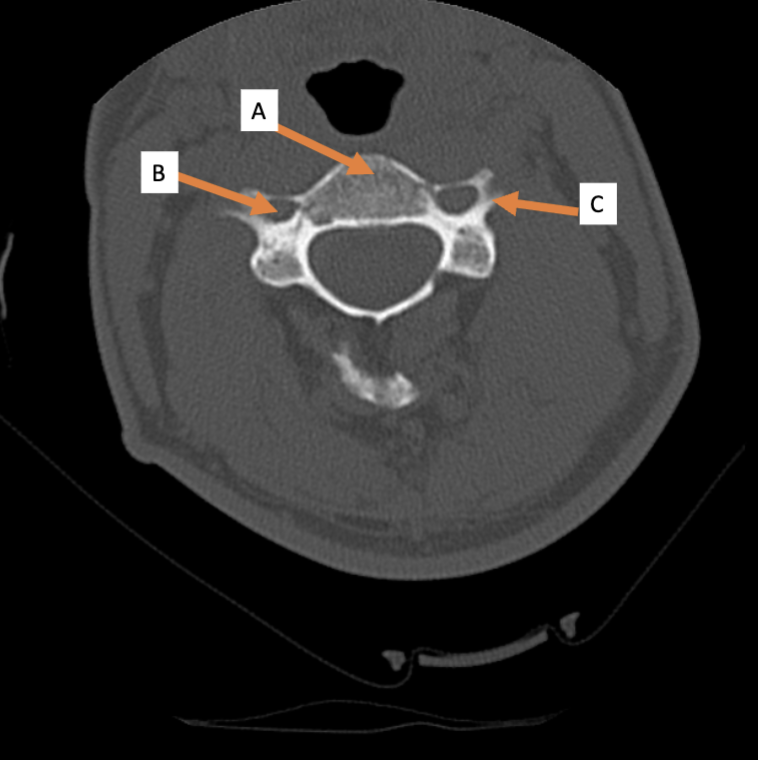

A. Identify structure

Transverse foramen; Vertebral a.

B. Identify structure; What goes through this feature?

Transverse process

C. Identify structure